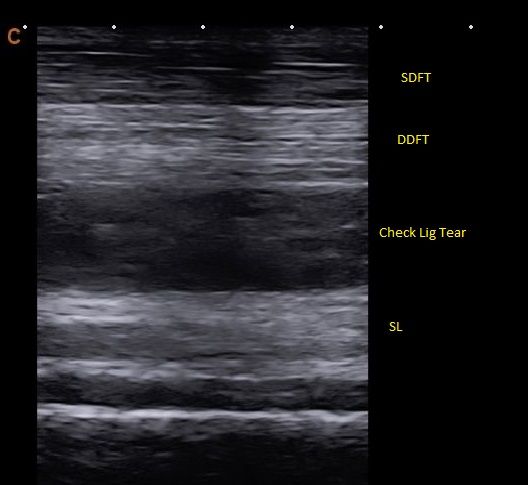

- Digital Ultrasound